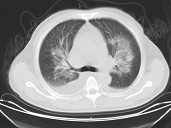

- 单项选择题男,32岁, CT图像如图,最可能的诊断为 ( )

A、肺水肿并双侧胸腔积液

B、周围型肺癌

C、肺动静脉瘘

D、肺错构瘤

E、炎性假瘤